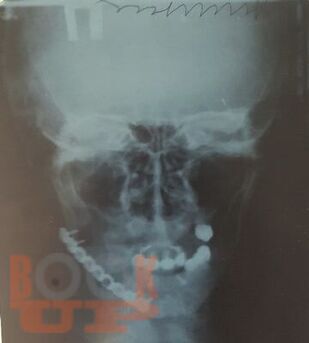

В учебном пособии представлены основные методы дополнительного исследования в челюстно-лицевой хирургии в соответствии с действующим учебным планом и программой обучения студентов-стоматологов.

Дополнительные методы исследования в челюстно-лицевой хирургии представлены лучевыми, ультразвуковыми методами диагностики, а также специальными методиками, позволяющими детализировать патологию зубочелюстной системы пациента с целью постановки окончательного диагноза и составления плана лечения.